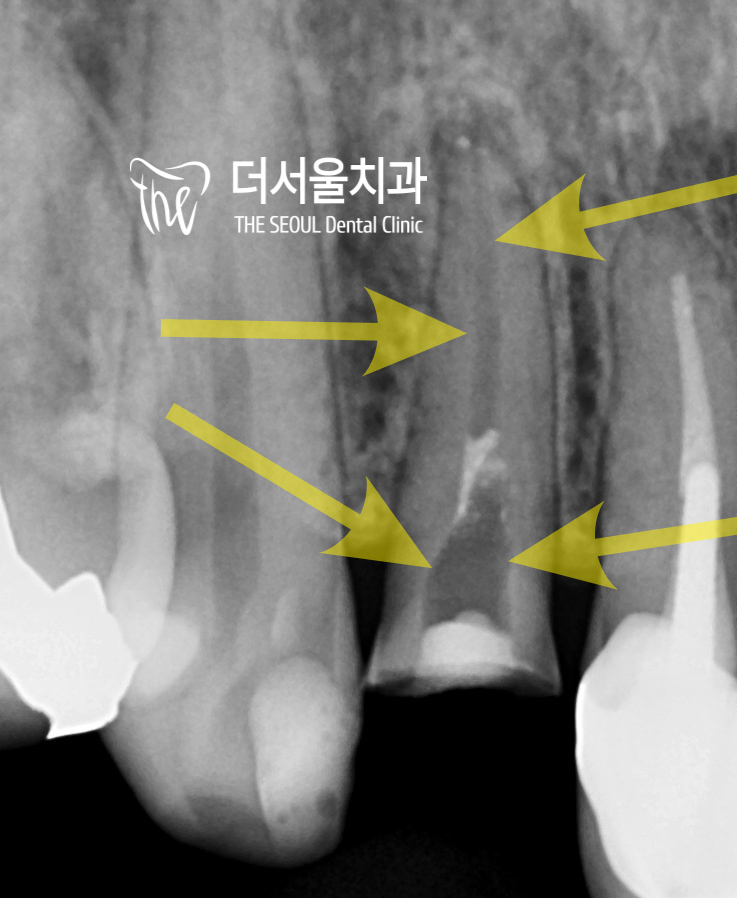

근데 문제가 또 있네요.

apical lesion 이라 해서,

뿌리 끝에 병소도 같이 맺혀있는 것을

볼 수 있습니다.

a. 염증이 있는 상태이다.

b. 치관이 사라져서 포스트 코어를 해야 된다.

c. 재치료를 해야 되는 상황.

이런 것들을 종합적으로 보게 되면,

사실 재치료를 해드린다 한들

그 예후가 좋지 않을 가능성이 높습니다.

뿌리 끝 염증(apical lesion) 도 사라졌고

앞니라서 예쁘게도 만들어드렸습니다.